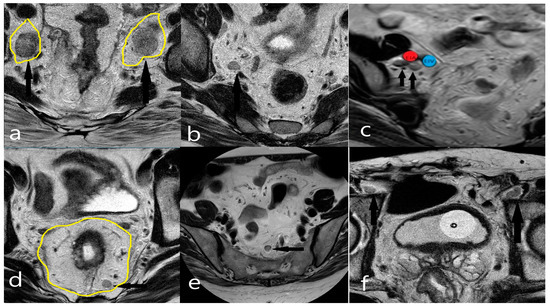

2.5. Anatomical Classification of Lateral Lymph Nodes and Classification of Pathological Lymph Nodes Based on Size